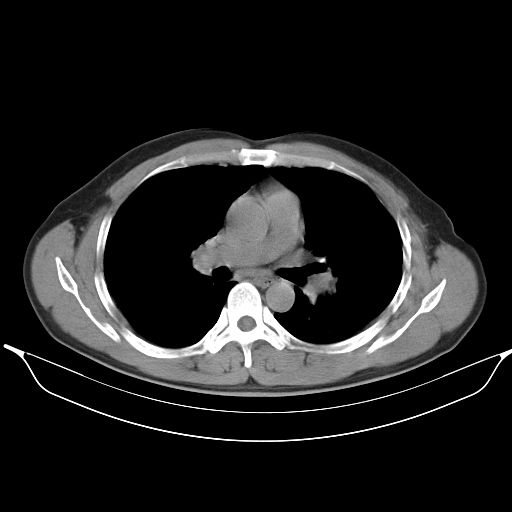

标题: CT25490:男,40岁,体检发现;无其它不适。 [打印本页]

标题: CT25490:男,40岁,体检发现;无其它不适。

支持 !考虑右下肺周围性肺癌并肺内多发转移,纵隔淋巴结转移,(气管前腔静脉后,隆突下,主动脉弓下都有了)